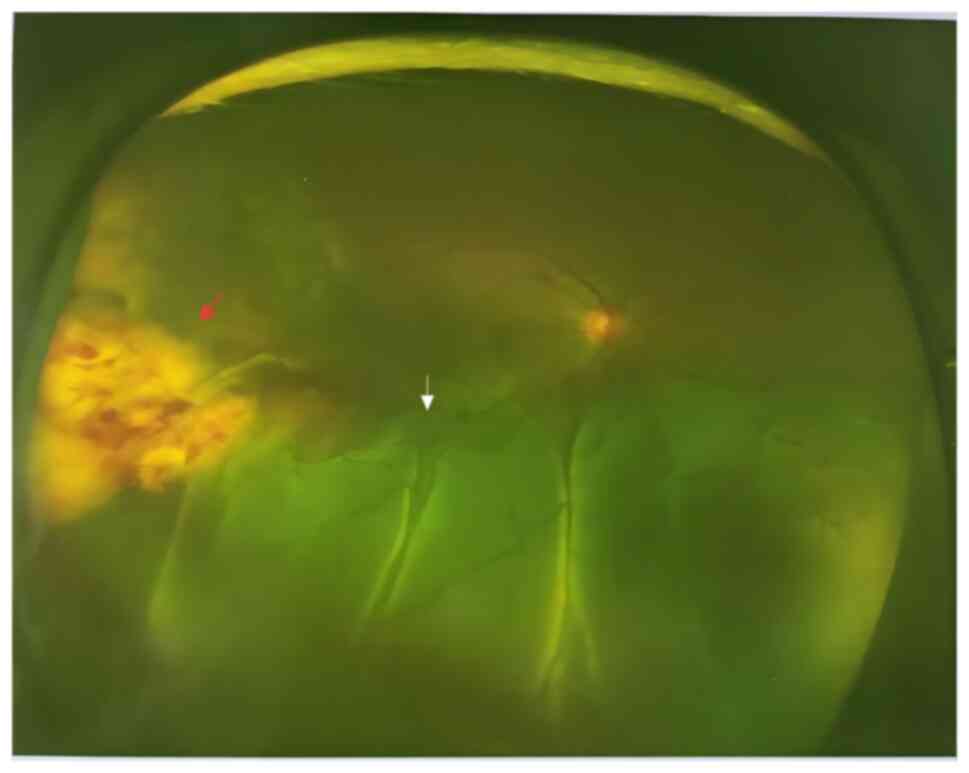

Figure 1

Fundus photograph of the right eye at

initial consultation shows a subretinal lesion temporal to the

optic disc (red arrow), with inferior retinal detachment (white

arrow).